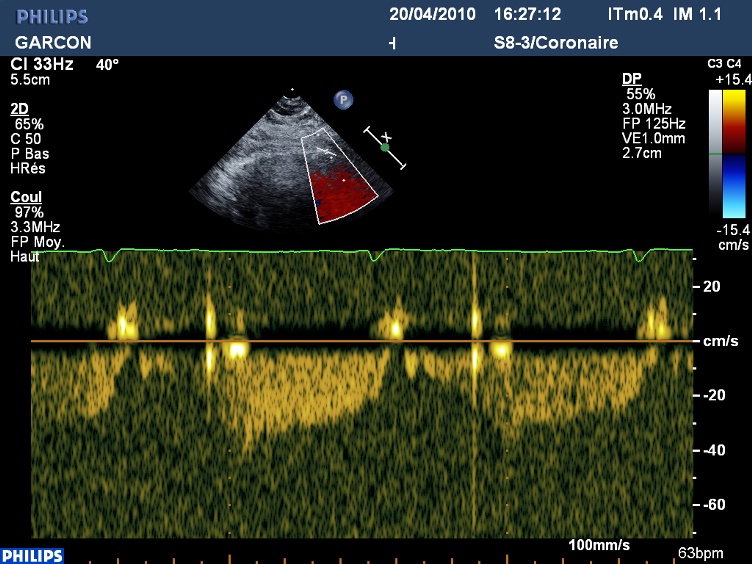

En Doppler couleur : l’IVA distale parait circuler à l’envers!(le flux est bleu, fuyant le capteur en diastole)

Et le flux en Doppler pulsé est négatif.

L’IVA circule bien à l’envers, l’occlusion chronique de l’IVA moyenne avec reprise par collateralité droite gauche sera confirmée plus tard par la coronarographie.

Très belle pente diastolique, même à l’envers, hélas trop rarement aperçue. On obtient, chez les pontées, des résultats similaires en effectuant le Doppler de la mammaire pontée.

Le doppler couleur : l’échelle des vitesses doit être diminuer entre 15 et 20 cm/sec. Il faut parfois ajouter un peu de persistance/lissage pour deviner mieux le trajet, et il faut adapter les réglages pour obtenir la puissance d’émission la plus élevée. Pour le signal doppler pulsé, il faut diminuer les filtres (basses vélocités) et la taille de l’échantillon de l’ordre de 1,5 à 2 mm.